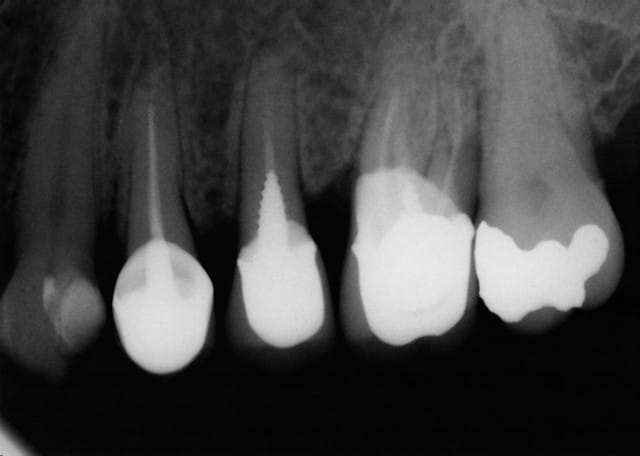

J'ai déjà récupéré de nombreuses racines à ce stade et les ai utilisées comme piliers de bridges ou les ai couronnées, dans la mesure ou l'ancrage alvéolaire était solide et en respectant les furcations pour y assurer l'hygiène.

La gencive lasérisée devient très ferme avec le temps et le déchaussement se stabilise. Ces restaurations se comportent bien sur un recul de plusieurs années.

Un exemple: une 46 avec furcation linguale dénudée après lasérisation et restauration par une endocouronne céromère réalisée il y a 9 ans et sans signe clinique avec une excellente attache gingivale malgré la perte osseuse, les 3 avant dernières images ont été prises lors d'un contrôle en mars dernier ...

9 années pour cette patiente de 90 ans, cela vaut bien le coup d'essayer vous ne croyez-pas? (dernière radio)

Avec le laser, on devient bien plus conservateur...